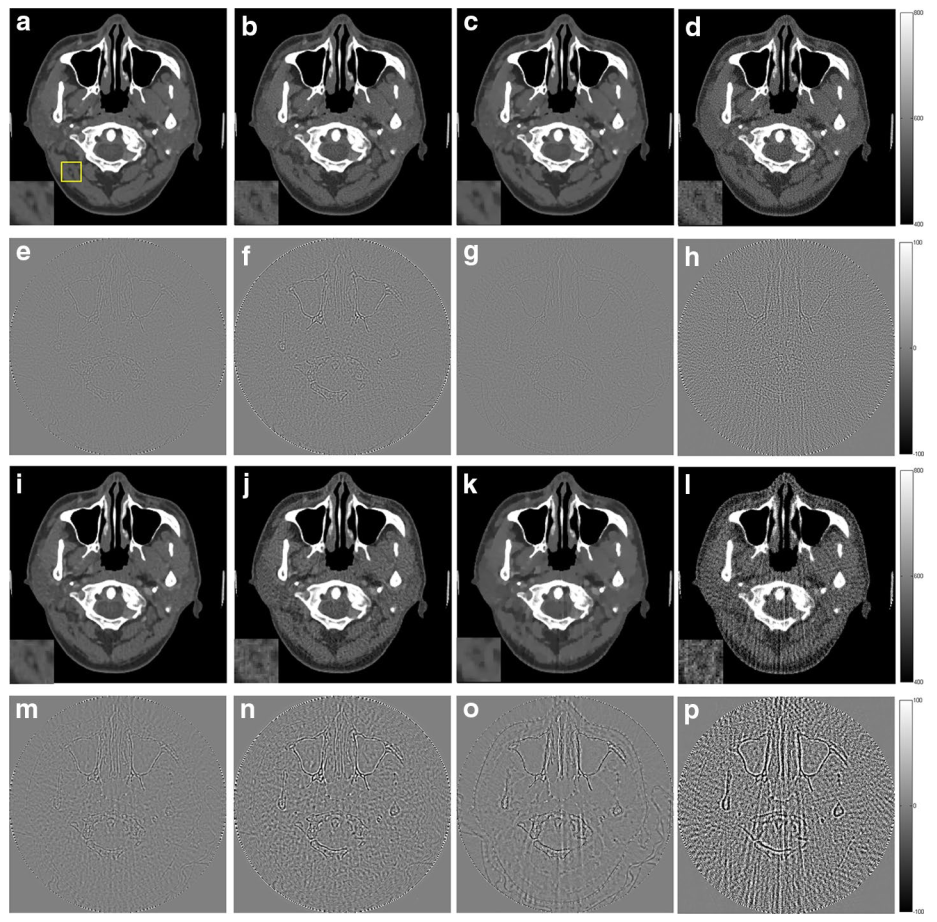

1 人体头部切片的重建结果。a-d180个采样角度下的重建结果,从左到右分别为本文提出的L1-DL算法,ADSIRGPBBSARTe-h为图像(a-d)与原始图像的差异图像;i-l90个采样角度下的重建结果,从左到右分别为本文提出的L1-DL算法,ADSIRGPBBSARTm-p为图像(i-l)与原始图像的差异图像.由图可见,本文提出的算法得到的重建图像在黄色边框的放大区域,更好的保留了细节信息,同时重建图像和原始图像的差异最小,这种优势在进一步降低采样率时(90个采样角度)表现的更加明显。

实验结果表明,与已有的基于L2范数的字典学习重建算法(ADSIR)以及其他两种典型的重建算法(GPBBSART)相比,提出的算法得到的重建结果更精确,尤其在进一步降低采样率的条件下,得到的结果与对比算法相比有明显的提升,说明L1范数的约束对于图像稀疏特性提取的有效性。